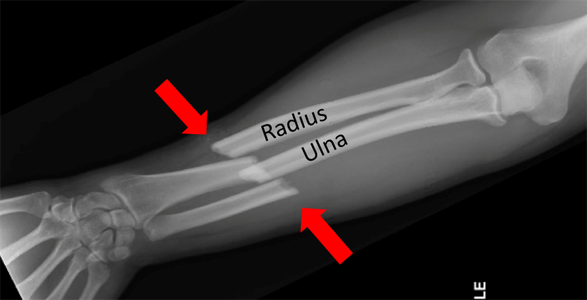

Product id: Forearm fracture on sale

Adult Forearm Fractures OrthoInfo AAOS on sale, Forearm Fracture Orthopaedic Trauma Association OTA on sale, Radius and Ulnar Shaft Fractures Trauma Orthobullets on sale, Adult Forearm Fractures OrthoInfo AAOS on sale, Pediatric Both Bone Forearm Fractures Commack NY Forearm on sale, Forearm Fracture Brandon P. Donnelly MD on sale, Forearm fracture Radiology Reference Article Radiopaedia on sale, Both Bone Forearm Fracture Pediatric Pediatrics Orthobullets on sale, Forearm Fracture Orthopaedic Trauma Association OTA on sale, Ten year old male child who sustained right both bone unstable on sale, Forearm Fractures in Children Types and Treatments OrthoInfo on sale, Adult Forearm Fractures Physioflow PT Physical Therapy on sale, Forearm Fractures May Signal Intimate Partner Violence Imaging on sale, Let s play Forearm fractures Radiology Key on sale, ICE 001 Forearm injury LITFL ICE Clinical Cases on sale, Forearm Fracture Management in the ED Practice Essentials on sale, Forearm Fractures Core EM on sale, Management of pediatric forearm fractures what is the best on sale, Both bone forearm fracture with rotation Radiology Case on sale, Fore Arm Fracture Drsinghphysiocare on sale, Broken Arm Fractured Arm Symptoms Treatment Recovery on sale, Childhood Forearm Breaks Resulting from Mild Trauma May Indicate on sale, Forearm Fractures Dr Carrie Kollias MD FRCSC FRACS Orthopaedic on sale, Treatment of nonunion after forearm fractures in children a on sale, Forearm fracture WikEM on sale, Ulna Fracture Treatment Dallas Frisco Prosper Wylie SPORT on sale, Forearm fracture on sale, Forearm Radius and Ulna Fractures Reno Orthopedic Center on sale, Pediatric Forearm Fracture Denver CO Elbow Fracture Aurora on sale, Kid s Forearm Fracture Raleigh Hand Surgery Joseph J on sale, Greenstick Fractures of the mid Radial and Ulnar Diaphysis with on sale, Forearm Fracture Brandon P. Donnelly MD on sale, Forearm Fractures The Bone School on sale, Imaging results of the patient s right forearm fracture at initial on sale, Forearm Fracture Solutions Acumed on sale.

Adult Forearm Fractures OrthoInfo AAOS on sale, Forearm Fracture Orthopaedic Trauma Association OTA on sale, Radius and Ulnar Shaft Fractures Trauma Orthobullets on sale, Adult Forearm Fractures OrthoInfo AAOS on sale, Pediatric Both Bone Forearm Fractures Commack NY Forearm on sale, Forearm Fracture Brandon P. Donnelly MD on sale, Forearm fracture Radiology Reference Article Radiopaedia on sale, Both Bone Forearm Fracture Pediatric Pediatrics Orthobullets on sale, Forearm Fracture Orthopaedic Trauma Association OTA on sale, Ten year old male child who sustained right both bone unstable on sale, Forearm Fractures in Children Types and Treatments OrthoInfo on sale, Adult Forearm Fractures Physioflow PT Physical Therapy on sale, Forearm Fractures May Signal Intimate Partner Violence Imaging on sale, Let s play Forearm fractures Radiology Key on sale, ICE 001 Forearm injury LITFL ICE Clinical Cases on sale, Forearm Fracture Management in the ED Practice Essentials on sale, Forearm Fractures Core EM on sale, Management of pediatric forearm fractures what is the best on sale, Both bone forearm fracture with rotation Radiology Case on sale, Fore Arm Fracture Drsinghphysiocare on sale, Broken Arm Fractured Arm Symptoms Treatment Recovery on sale, Childhood Forearm Breaks Resulting from Mild Trauma May Indicate on sale, Forearm Fractures Dr Carrie Kollias MD FRCSC FRACS Orthopaedic on sale, Treatment of nonunion after forearm fractures in children a on sale, Forearm fracture WikEM on sale, Ulna Fracture Treatment Dallas Frisco Prosper Wylie SPORT on sale, Forearm fracture on sale, Forearm Radius and Ulna Fractures Reno Orthopedic Center on sale, Pediatric Forearm Fracture Denver CO Elbow Fracture Aurora on sale, Kid s Forearm Fracture Raleigh Hand Surgery Joseph J on sale, Greenstick Fractures of the mid Radial and Ulnar Diaphysis with on sale, Forearm Fracture Brandon P. Donnelly MD on sale, Forearm Fractures The Bone School on sale, Imaging results of the patient s right forearm fracture at initial on sale, Forearm Fracture Solutions Acumed on sale.